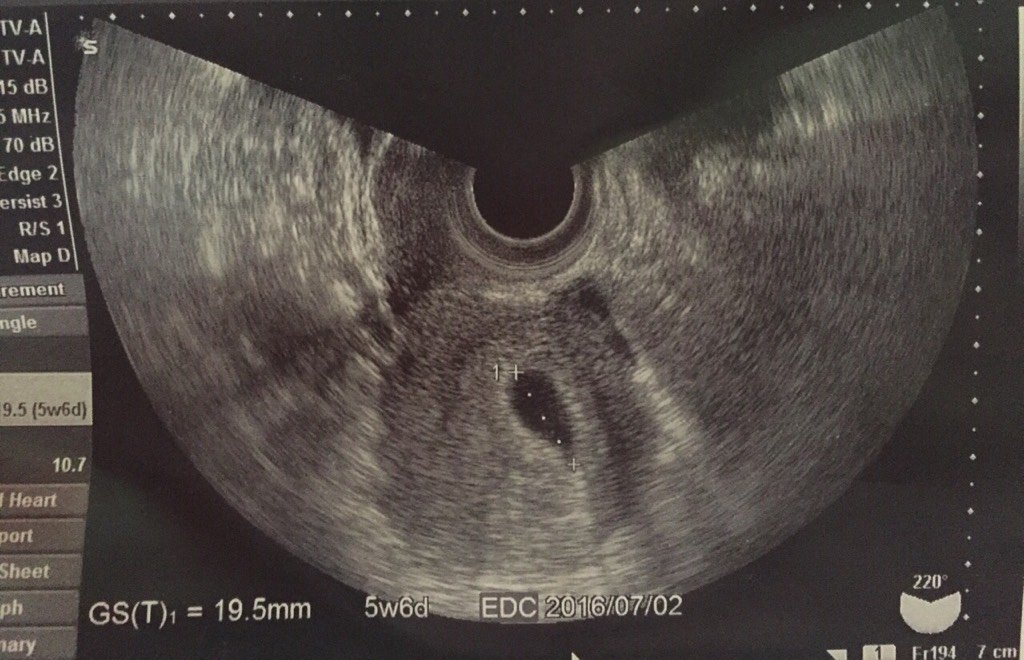

今天怀孕5周6天,去打b超,只有卵黄囊,还没有胎芽胎心,正常吗?

图片尺寸576x1024